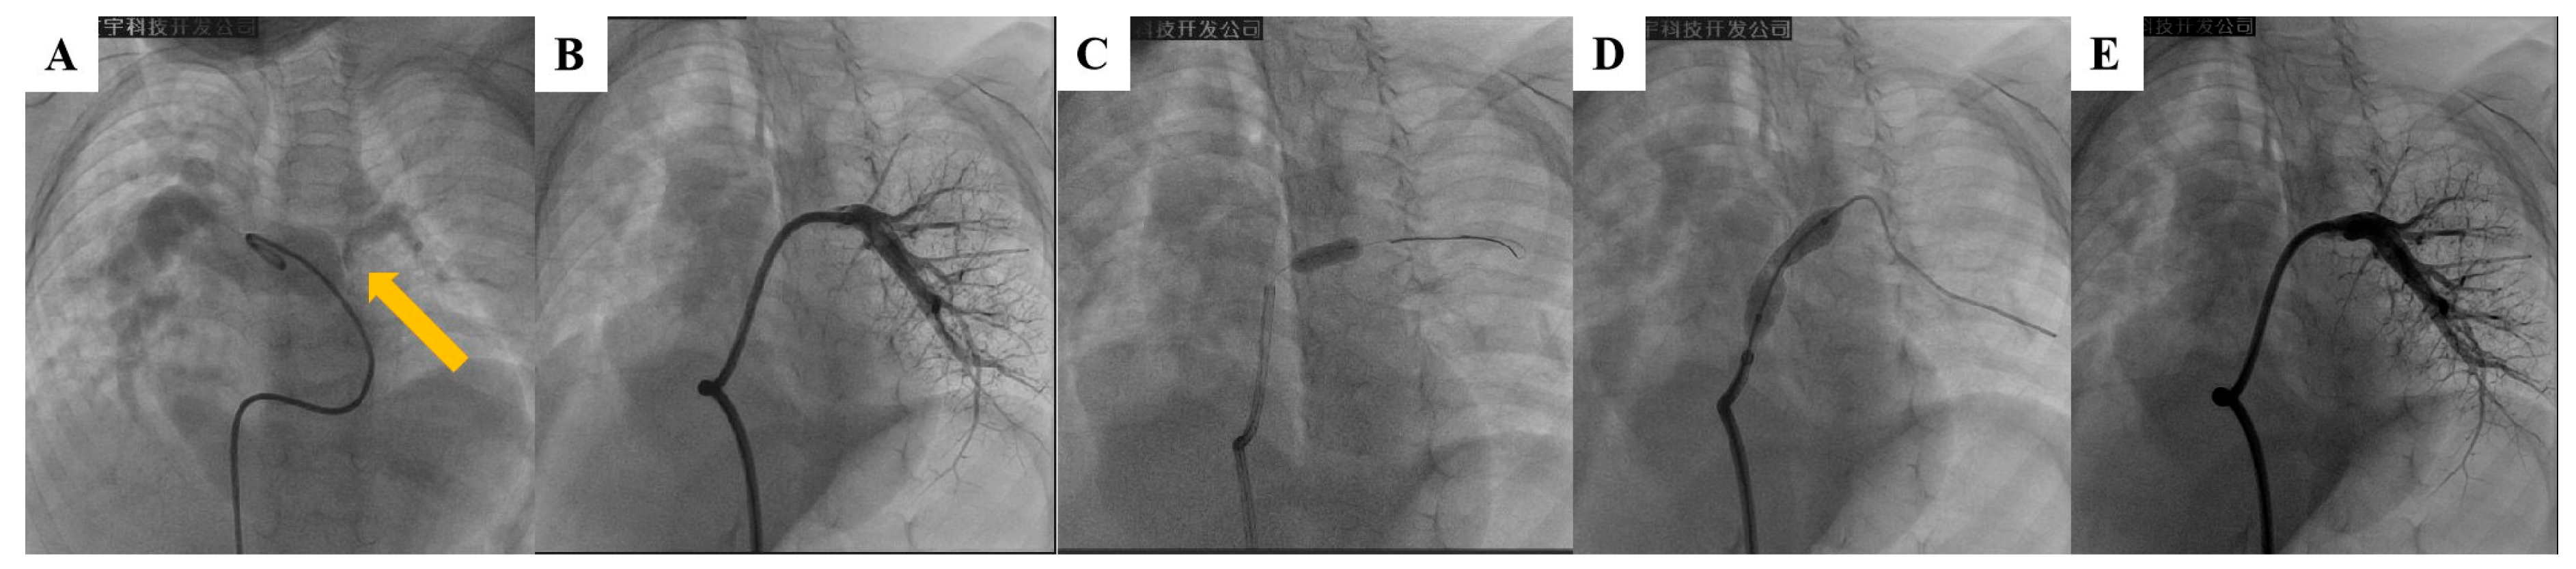

The percutaneous stent implantation procedure for PAS has been described in detail in previous reports [14,15,16]. The operation was performed under general anesthesia in all patients. Intravenous heparin (100 IU/kg) and prophylactic antibiotic (cefazolin 50 mg/kg) were administered. A diagnostic catheterization was performed to evaluate hemodynamic and morphological data using the femoral veins as access vessels. RV and pulmonary artery angiography were performed to obtain the following measurements: stenosis segment diameter, diameter of the segment adjacent to the stenosis, and distance from the stenosis to the opening of the left or right pulmonary artery and to the lower branch vessels. An appropriate stent was selected based on the angiographic findings. The stent size did not exceed the diameter of the normal pulmonary artery adjacent to the stenosis, while its length did not exceed the distance from the opening of the left or right pulmonary artery to the lower branch vessels. Angiography was performed after the stents were delivered to the stenotic lesion to confirm the correct position. The balloon was then inflated to expand the stent to the desired diameter. Coronary balloon pre-dilation was performed prior to stent implantation if the target vessel exhibited severe stenosis (Fig. 1). Repeat angiography and hemodynamic measurements were carried out to evaluate the acute outcome of stent implantation.

Figure 1: Percutaneous stent implantation in a case of left pulmonary artery (LPA) stenosis. (A) Proximal stenosis of LPA (arrow); (B) Distal LPA segment adjacent to the narrowing site as shown on pulmonary angiography. (C) Pre-dilation of stenosis with a 3-mm coronary balloon; (D) Implantation of 8 mm × 27 mm stent at stenosis; (E) Repeat pulmonary angiography demonstrating stenosis resolution and pulmonary perfusion improvement after stent implantation.